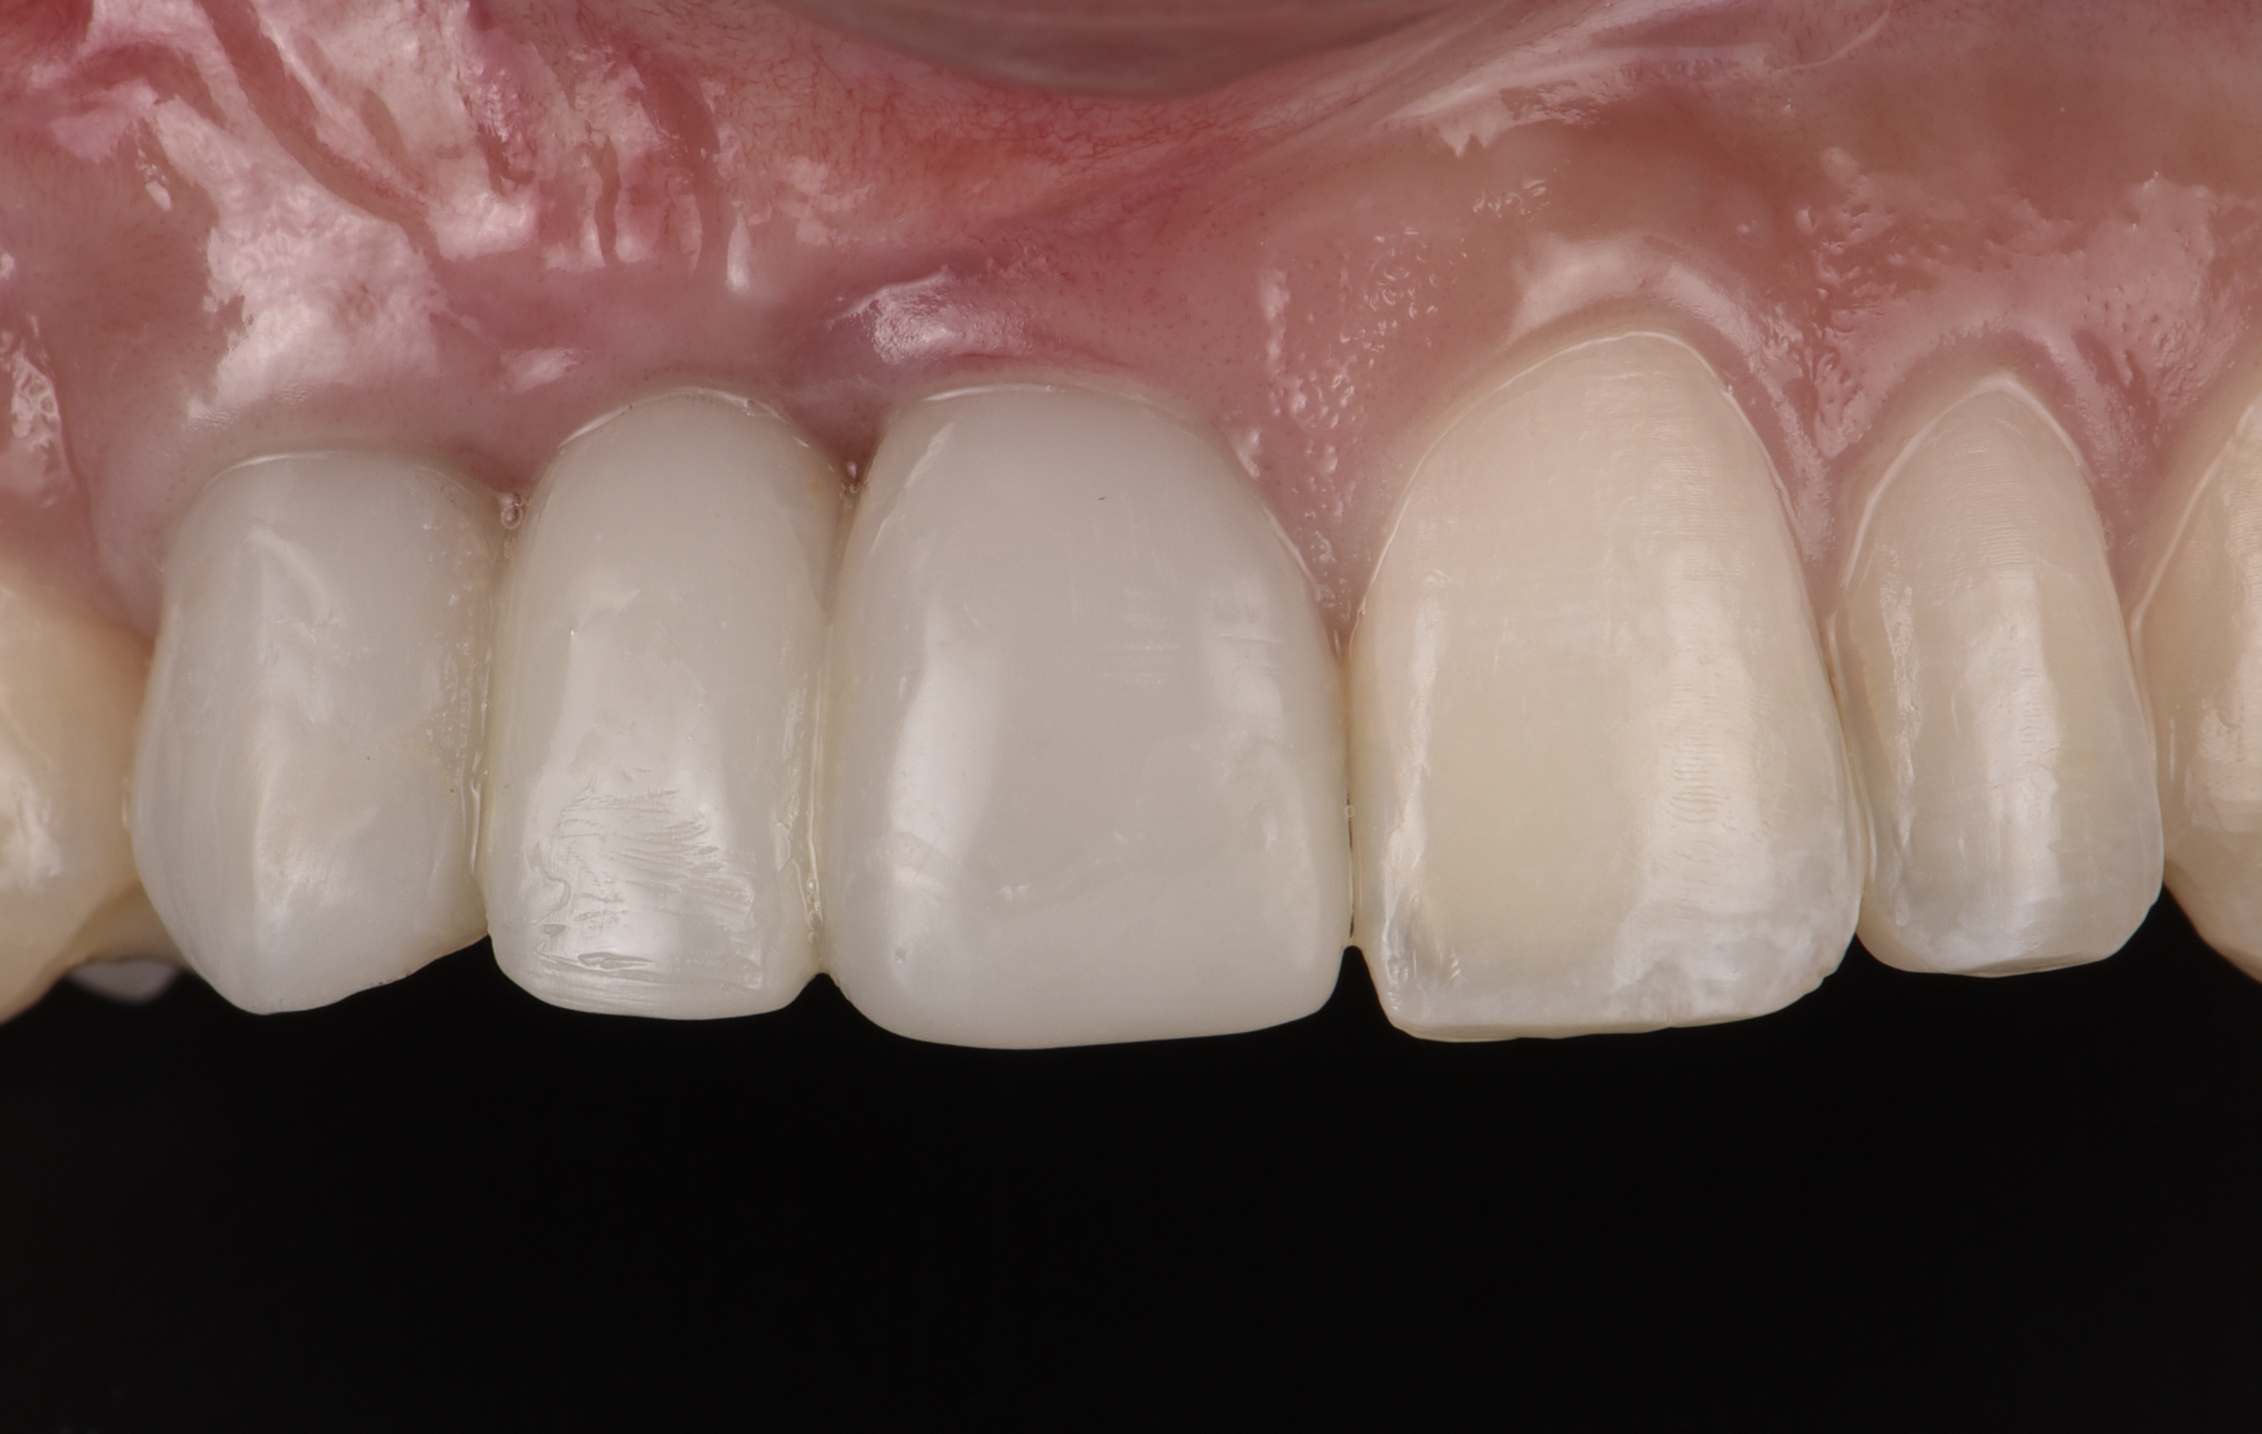

At the patient’s return visit 3 months after implant placement, the composite overlays were removed and the incisal edges of the provisional restoration were modified to approximate the length of the contralateral teeth. The patient reported no complaints, discomfort, or symptomatology throughout the osseointegration period. The implants were stable, and all discernable clinical parameters were within normal limits. The radiographic assessment revealed adequate bone-to-implant contact and osseous crest levels. Similarly, the peri-implant soft tissues displayed a healthy appearance and satisfactory gingival margin architecture (Figure 24 through Figure 27).